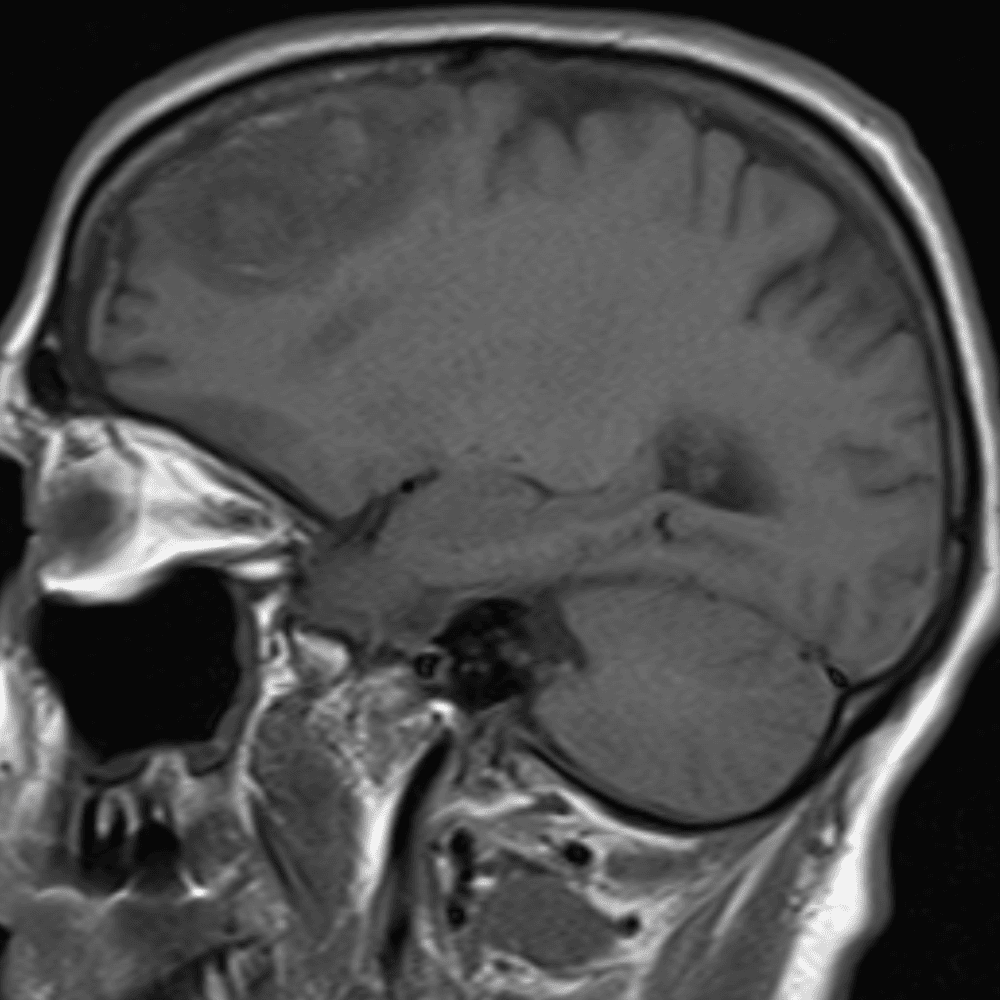

๋‹น์ง ์‹œ ํ”ํžˆ ๋ณผ ์ˆ˜ ์žˆ๋Š” ์‚ฌ๋ก€์˜ ์ „ํ˜•์ ์ธ ์˜ˆ๋ฅผ ํฌํ•จํ•ฉ๋‹ˆ๋‹ค.

39 ์‚ฌ๋ก€

์—ฐ์Šต

๋ฏธ๋ฌ˜ํ•˜๊ฑฐ๋‚˜ ์–ด๋ ค์šด ์‚ฌ๋ก€์™€ ์ผ๋ถ€ ์ •์ƒ ์‚ฌ๋ก€๋ฅผ ํฌํ•จํ•˜์—ฌ ๋‹น์ง์„ ์‹œ๋ฎฌ๋ ˆ์ด์…˜ํ•ฉ๋‹ˆ๋‹ค.

50 ์‚ฌ๋ก€